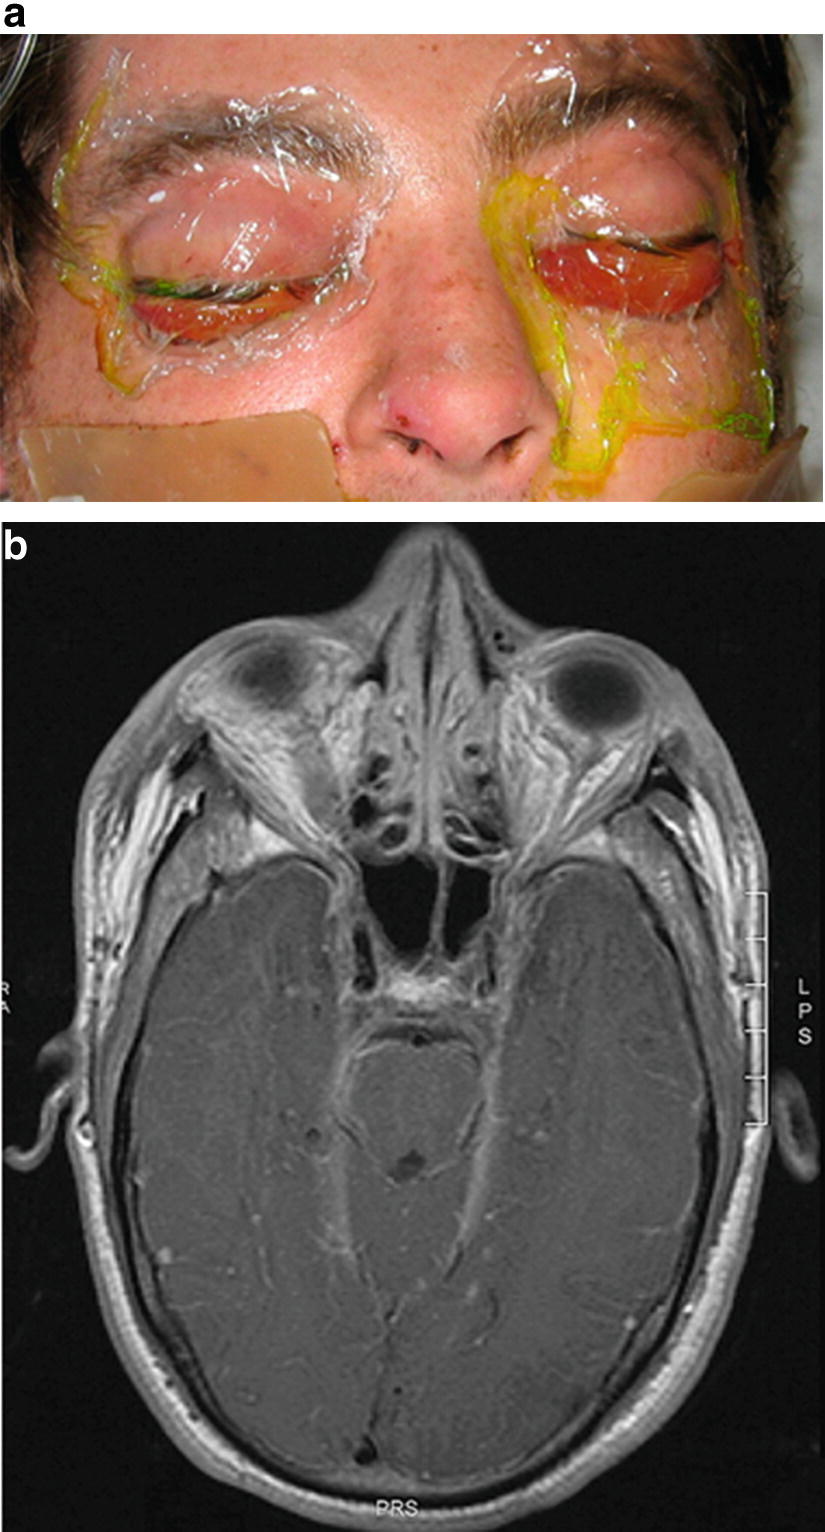

Loprinzi, regis professor of breast cancer research, division of medical oncology, mayo clinic, provides insight into the management of nasal. Nasal vestibulitis is not a serious condition, but in rare cases, it can cause severe complications if a person does not seek and receive treatment for it. Nasal vestibulitis refers to diffuse, shallow inflammation of nasal vestibular skin with bilateral onset. Ophthalmic neomycin, polymyxin, and bacitracin combination comes as an ointment to apply inside the lower lid of an infected eye. How much do you know about bell palsy?

Nasal Vestibulitis An Under Recognized And Under Treated Side Effect Of Cancer Treatment Springerlink from media.springernature.com Recognizing nasal vestibulitis in the primary care setting. This topic will focus on the clinical manifestations, evaluation, and treatment of nasal obstruction in adults. It should be treated immediately because it. The inner lining of the nose may become inflamed for several reasons, and constant irritation of the membranes will cause them to thin and weaken. How much do you know about bell palsy? Nasal vestibulitis is a bacterial infection that starts in the hair follicles of the nose. 2 common cold and influenza. Aggressive broad spectrum antibiotics may be used after the infected area has been drained of fluids.